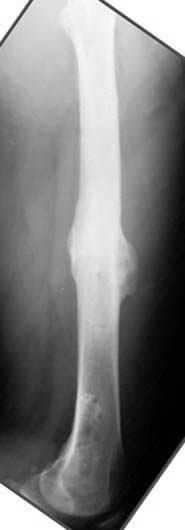

пластическая модель; и коррекция бедра аппаратом Илизарова.

Узкий к-м канал - тонкий гвоздь- усталостный перелом дистальных винтов - развитие нестабильности и как ее результат остеолиз вокруг гвоздя - деформация анатомической оси бедра. Похоже, что я понял почему аппарат, а не новый гвоздь:-)

ЕТ - Изначально костно-мозговой канал бедра был узкий, дальнейшее его рассверливание ещё больше скомпрометирует прочность бедра( латеральный кортекс дистального отломка уже истончен), приведет к дефекту наружной стенки - хотя это только мои догадки - хотелось бы знать мнение Джолдаса о выбранной тактике.